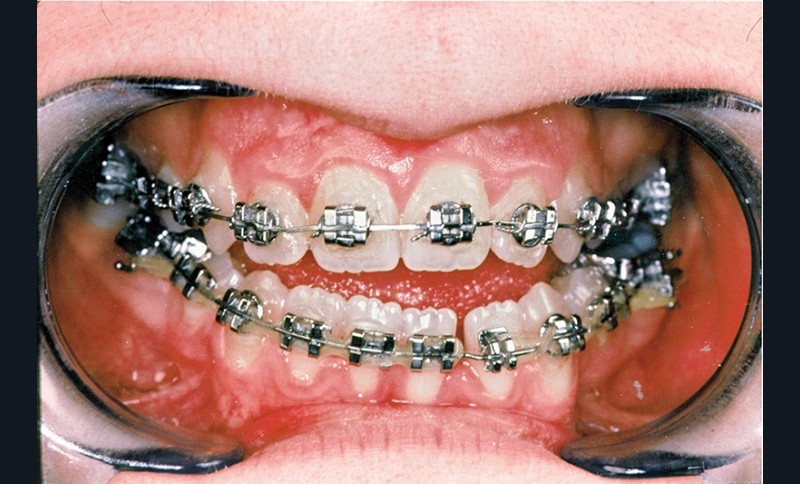

• une préparation orthodontique préchirurgicale avec extraction des quatre premières prémolaires qui a assuré la correction de l’encombrement, la décompensation de la malocclusion et l’harmonisation des formes d’arcades (fig. 4 et 5),